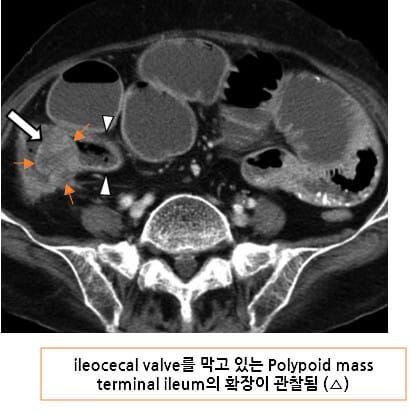

CT 소견 (Contrast-enhanced CT)

🔵 장벽 비후 (Bowel wall thickening)

암 부위의 장벽이 국소적으로 두꺼워지며, 조영증강되는 불균일한 덩어리로 관찰됩니다.

🔵 Annular constricting mass

암이 장을 원형으로 둘러싸며 협착을 유발하는 고전적 폐색 패턴입니다.

Kim, S. W., Shin, H. C., Kim, I. Y., Kim, Y. T., & Kim, C.-J. (2010). CT findings of colonic complications associated with colon cancer. Korean Journal of Radiology, 11(2), 211–221. https://doi.org/10.3348/kjr.2010.11.2.211